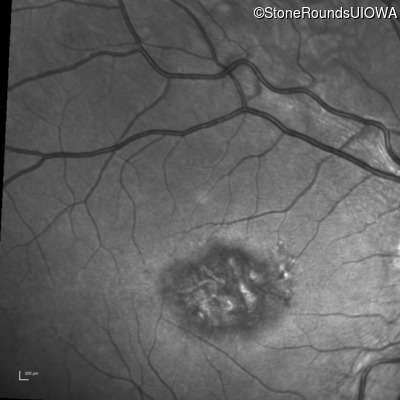

Blue Autofluorescence - Left - 20/125 sc

Exemplar